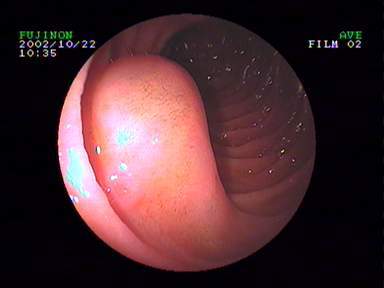

八、内镜下内痔硬化剂及套扎治疗

内镜套扎治疗及硬化治疗 适合I-III期 内痔,包括部分混合痔的微创治疗,疗效显著,与传统外科手术相比,超级微创、费用低、见效快,具有很大优势。

III度内痔 硬化剂及套扎术后